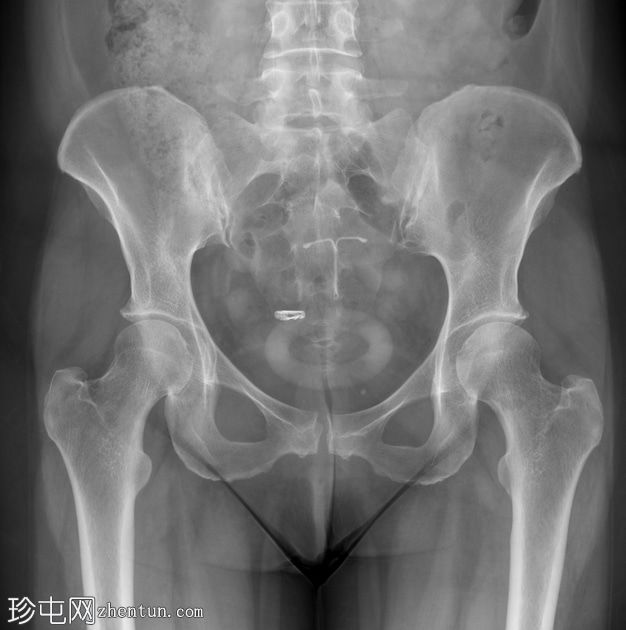

盆腔X线片显示盆腔内有多处器械。左侧盆腔旁中心位置可见宫内节育器(IUCD),中央环状子宫托,右侧附件区可见金属绝育夹(菲尔希夹)。

骶髂关节和髋关节骨关节炎程度轻微。

本例患者因保守治疗子宫脱垂而使用子宫托,此次检查意外发现盆腔内有其他器械,分别为单侧金属绝育夹和宫内节育器。